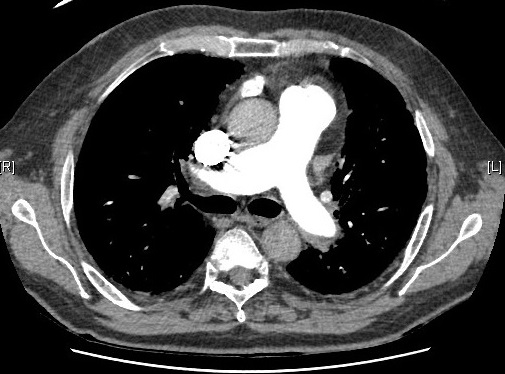

La Hipertensión Arterial Pulmonar es una enfermedad grave que afecta a la arterias pulmonares. Suele aparecer entre la 3ª y 4ª década de la vida y es más frecuente en mujeres. En el 6% de los casos existen antecedentes familiares de la enfermedad que se transmite siguiendo un patrón de herencia autosómico dominante con penetrancia reducida. […]